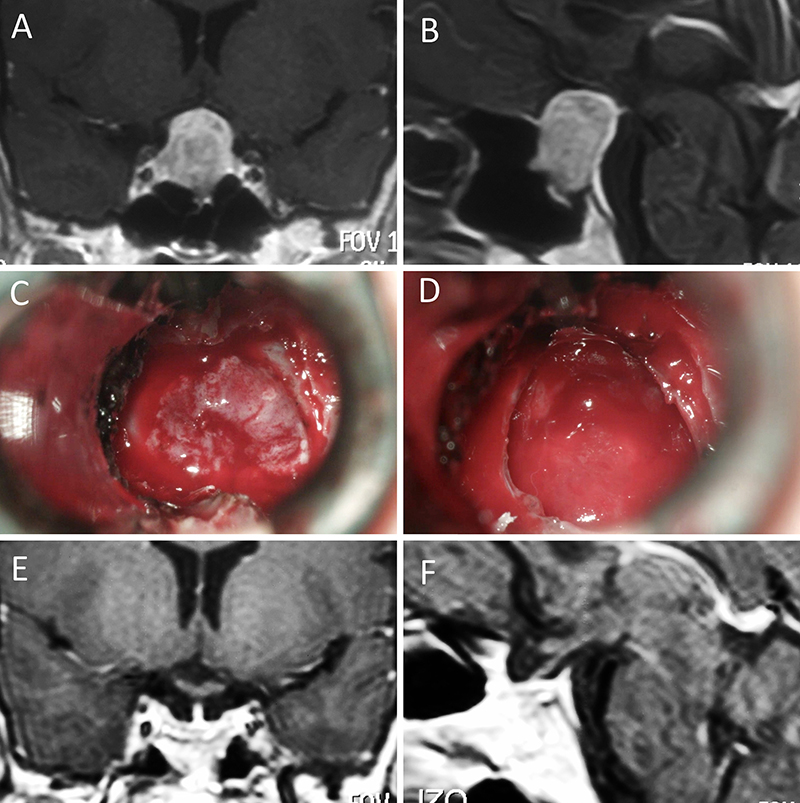

Figura 7: Acromegalia en mujer de 39 años. Con remisión bioquímica tras la cirugía. A-B: RM preoperatoria; C-D: intraoperatorio; E-F: RM postoperatoria.

Figura 8: Acromegalia en mujer de 50 años. Con remisión bioquímica tras la cirugía. A-B: RM preoperatoria; C-D: intraoperatorio; E-F: RM postoperatoria.